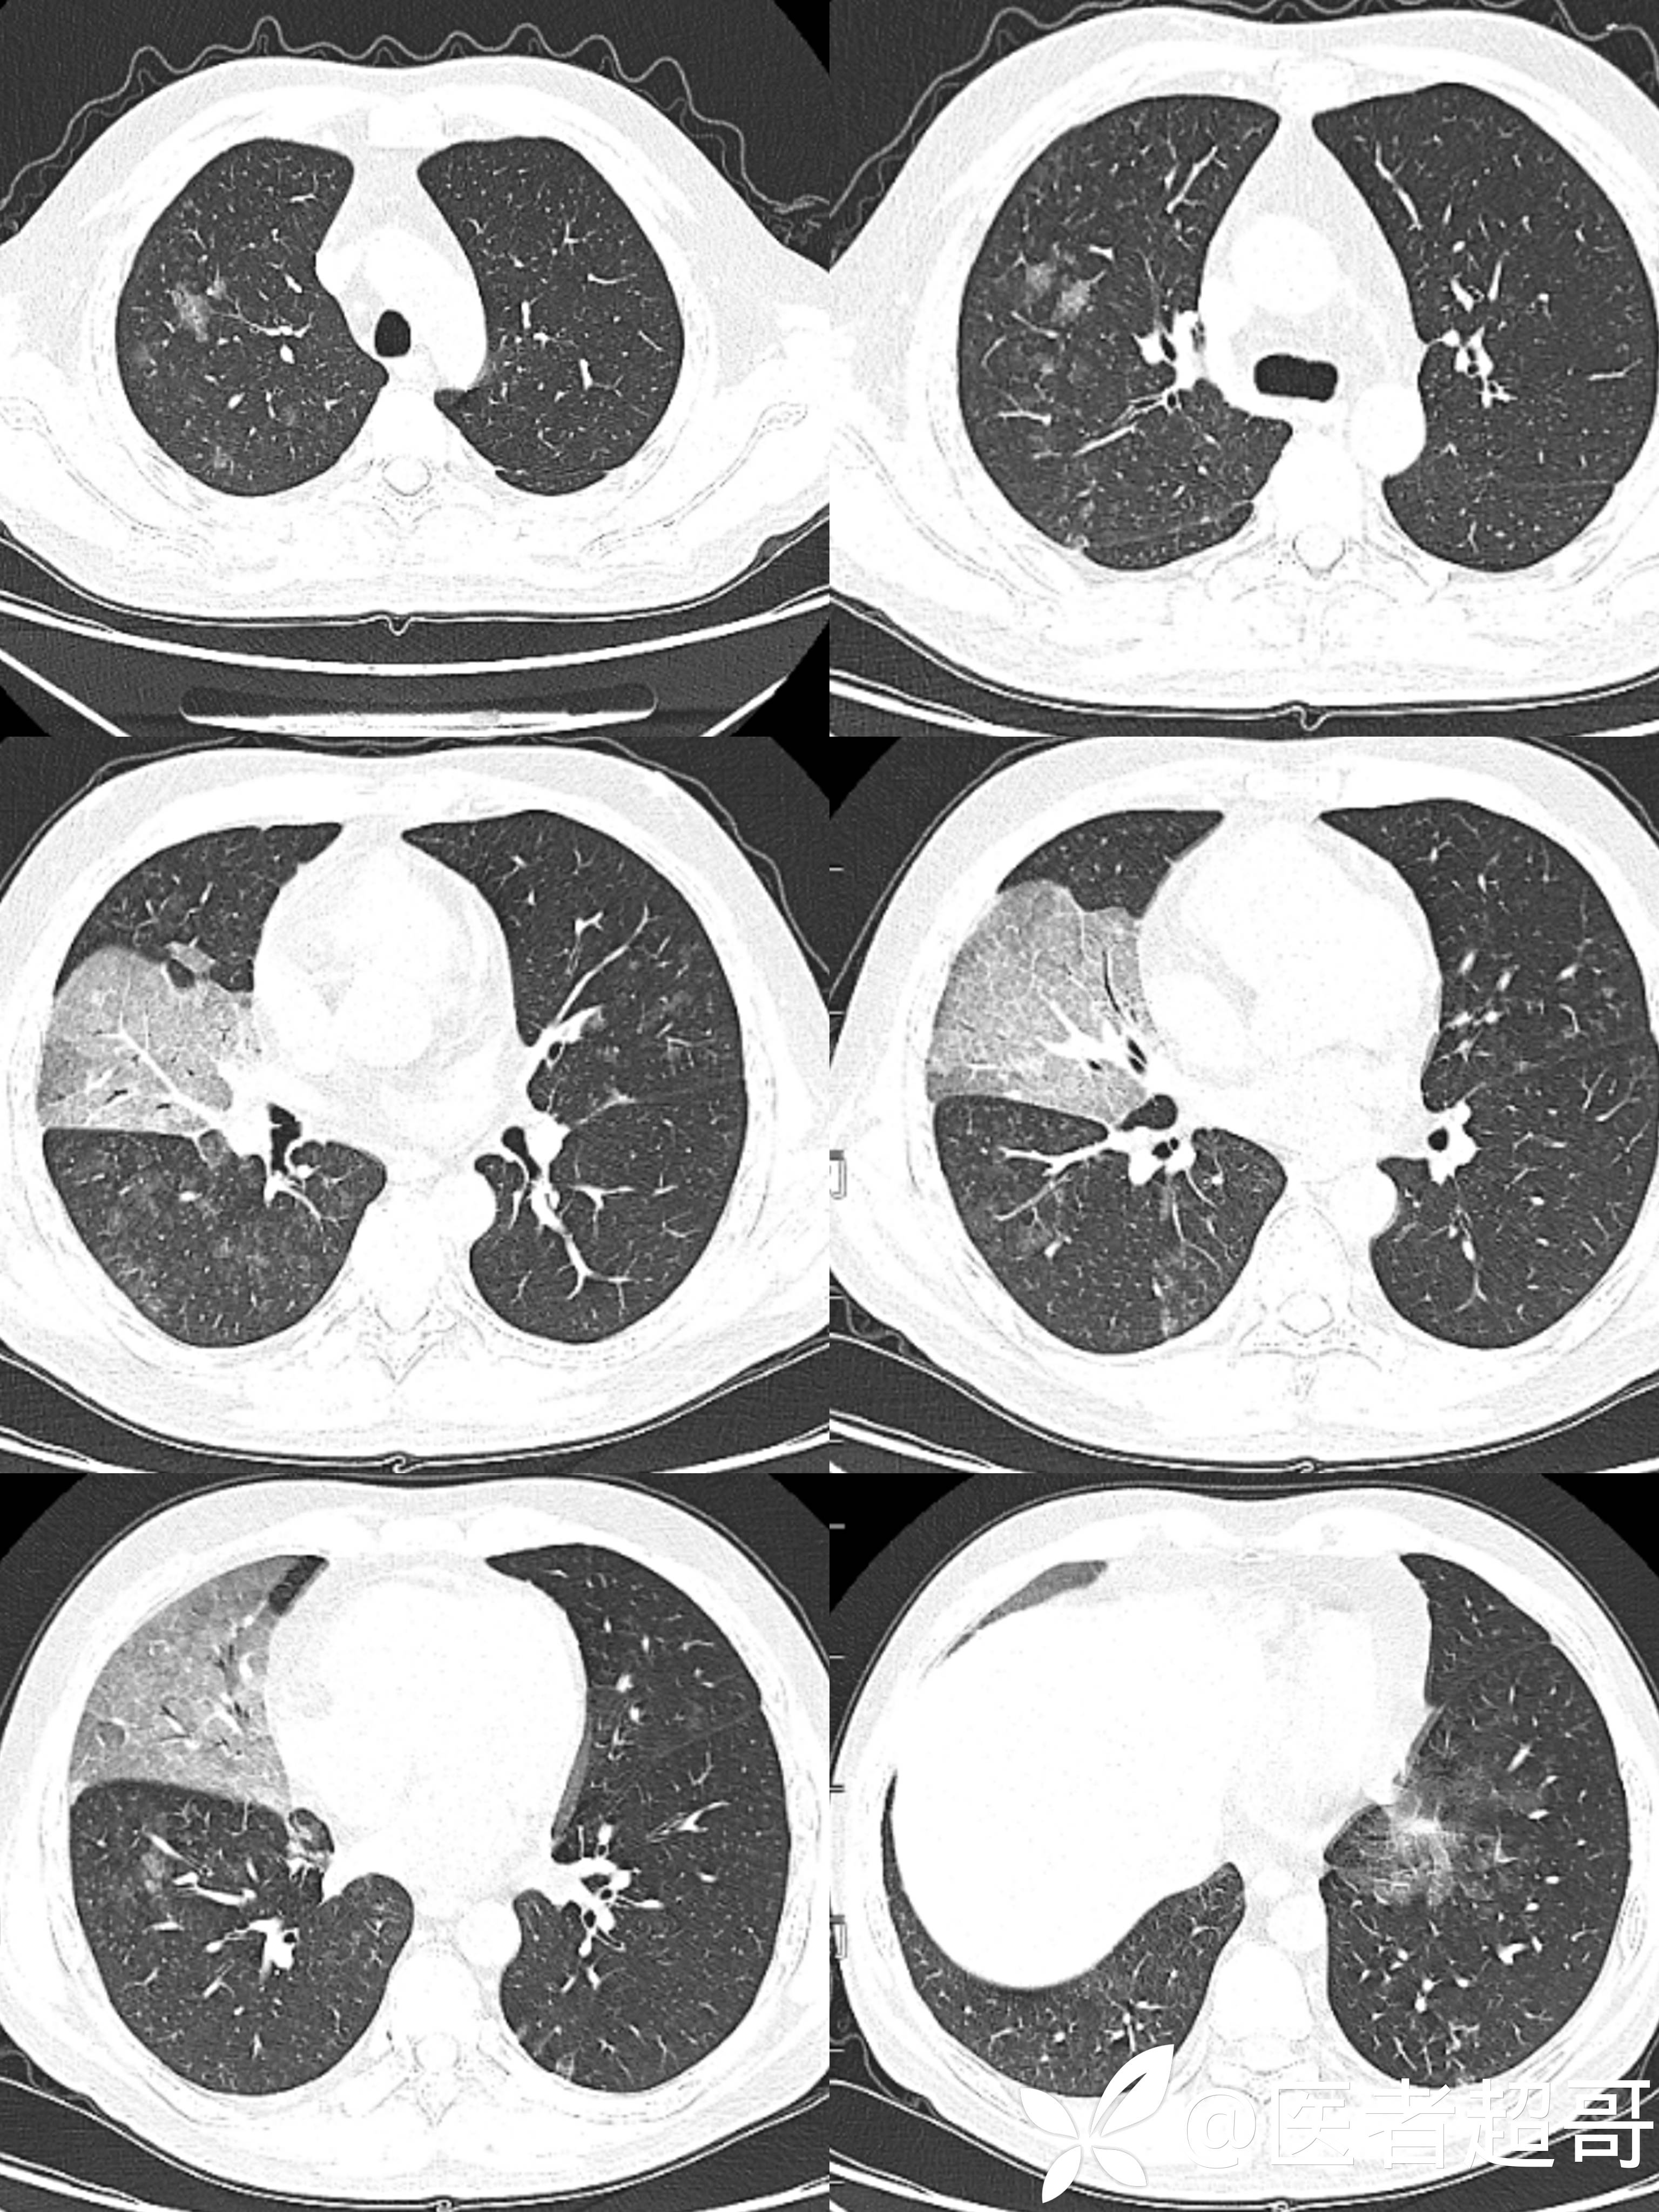

【影诊笔记526】确诊淋巴瘤两年,发现双肺病变八月余,行肺部CT,请分析~~~

男,37岁 ;因“确诊淋巴瘤两年,发现双肺病变八月余”入院

患者两年前因右侧鼻塞流涕,涕中带血于外院确诊“鼻NK/T淋巴瘤”,后规律放化疗,一年前评估复发,再行放化疗

患者因萎缩性鼻炎行薄荷油滴鼻后右侧卧位史3年

实验室检查:白细胞计数:7.37×10^9/L;红细胞计数:3.01×10^12/L↓;血红蛋白:87g/L↓;中性粒细胞比率:87.6%↑;淋巴细胞计数:0.42×10^9/L